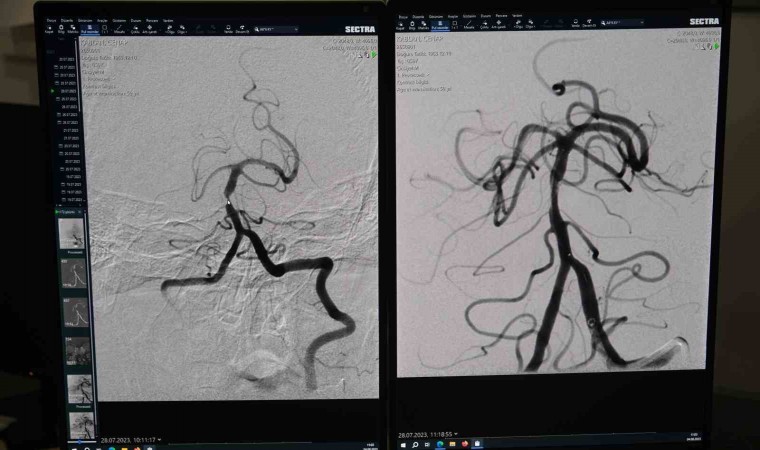

Dr. Öğr. Üyesi Yıldız, Nöroradyoloji açısından çok başarılı bir operasyon gerçekleştirdiklerini ifade ederek, "Hasta, tekrarlayan beyin inmesi atakları sebebiyle radyoloji bölümüne sevk edildi. Hastanın inme atakları ilaç tedavisine yanıt vermediği için yapılan anjiyografik incelemede beynin en önemli damarlarından biri olan beyin arka çukur ana atardamarında (baziler arterde) önemli bir darlık tespit ettik” diye konuştu.

Gerçekleştirdiği operasyona değinen Dr. Öğr. Üyesi Yıldız, “Hastanın tedavi planını yaptıktan sonra ilgili beyin damarına ulaşarak mikrokatater tekniği ile öncelikle balon yapıp damarı genişlettik. Daha sonra damarın uzun dönem daha rahat açık kalabilmesi için bu bölgeye bir stent yerleştirdik. Hastamız şu an sağlıklı bir şekilde nöroloji servisinde yatmaktadır. Hastamızın işlem öncesi sağ kol ve bacağında güçsüzlük vardı. Bacağındaki güçsüzlük tedavi sonrasında daha iyi bir duruma geldi. Kolu da ilerleyen dönemde fizik tedaviyle daha iyi bir hale gelecek. Kendisine geçmiş olsun dileklerimizi iletiyoruz” şeklinde konuştu.